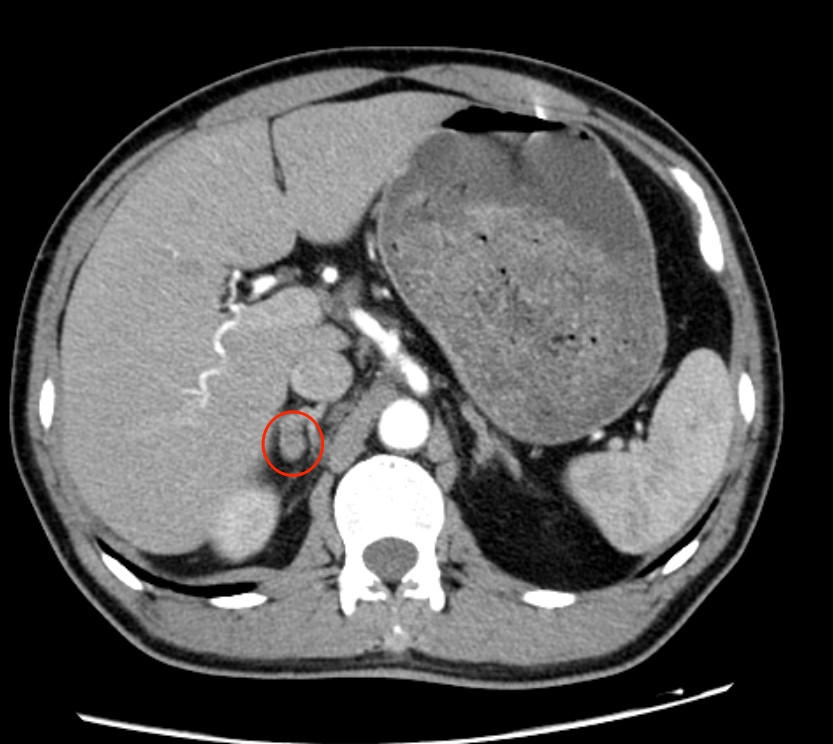

据悉,县第一人民医院内分泌科2019年成立了肾上腺亚专业组,自成立以来,在主任医师严健如的带领下,诊治较多肾上腺疾病患者,特别是原发性醛固酮增多症。以往,对于“原醛”的定位诊断多依赖于CT,但在实际操作中,临床发现约有11-16%的原醛患者,CT不能精准定位,为患者下一步选择手术治疗或者药物治疗带来了困惑。而双侧肾上腺静脉插管采血(AVS)技术则是区分单侧或双侧分泌最可靠、最准确的方法,以往由于本地未开展此项技术,这部分患者需到长沙等地做AVS,影响患者的进一步治疗。

严健如介绍,原发性醛固酮增多症是由肾上腺分泌的一种叫“醛固酮”的激素增多导致的疾病,通常与肾上腺的腺瘤或增生有关,可导致高血压、头晕、全身乏力、麻木等症状,更有严重者可出现呼吸困难、脑梗、心梗等并发症。在高血压患者中,原醛症占5%-15%,因此,有大量的原醛症患者被误诊为普通的高血压病,从而错过了可能“治愈高血压”的机会。因在临床容易被忽视,早期筛查非常重要,而原发性醛固酮增多症一旦确诊,明确类型直接决定了患者的治疗方式,AVS是目前国际公认的原发性醛固酮增多症分型和定位诊断的金标准。